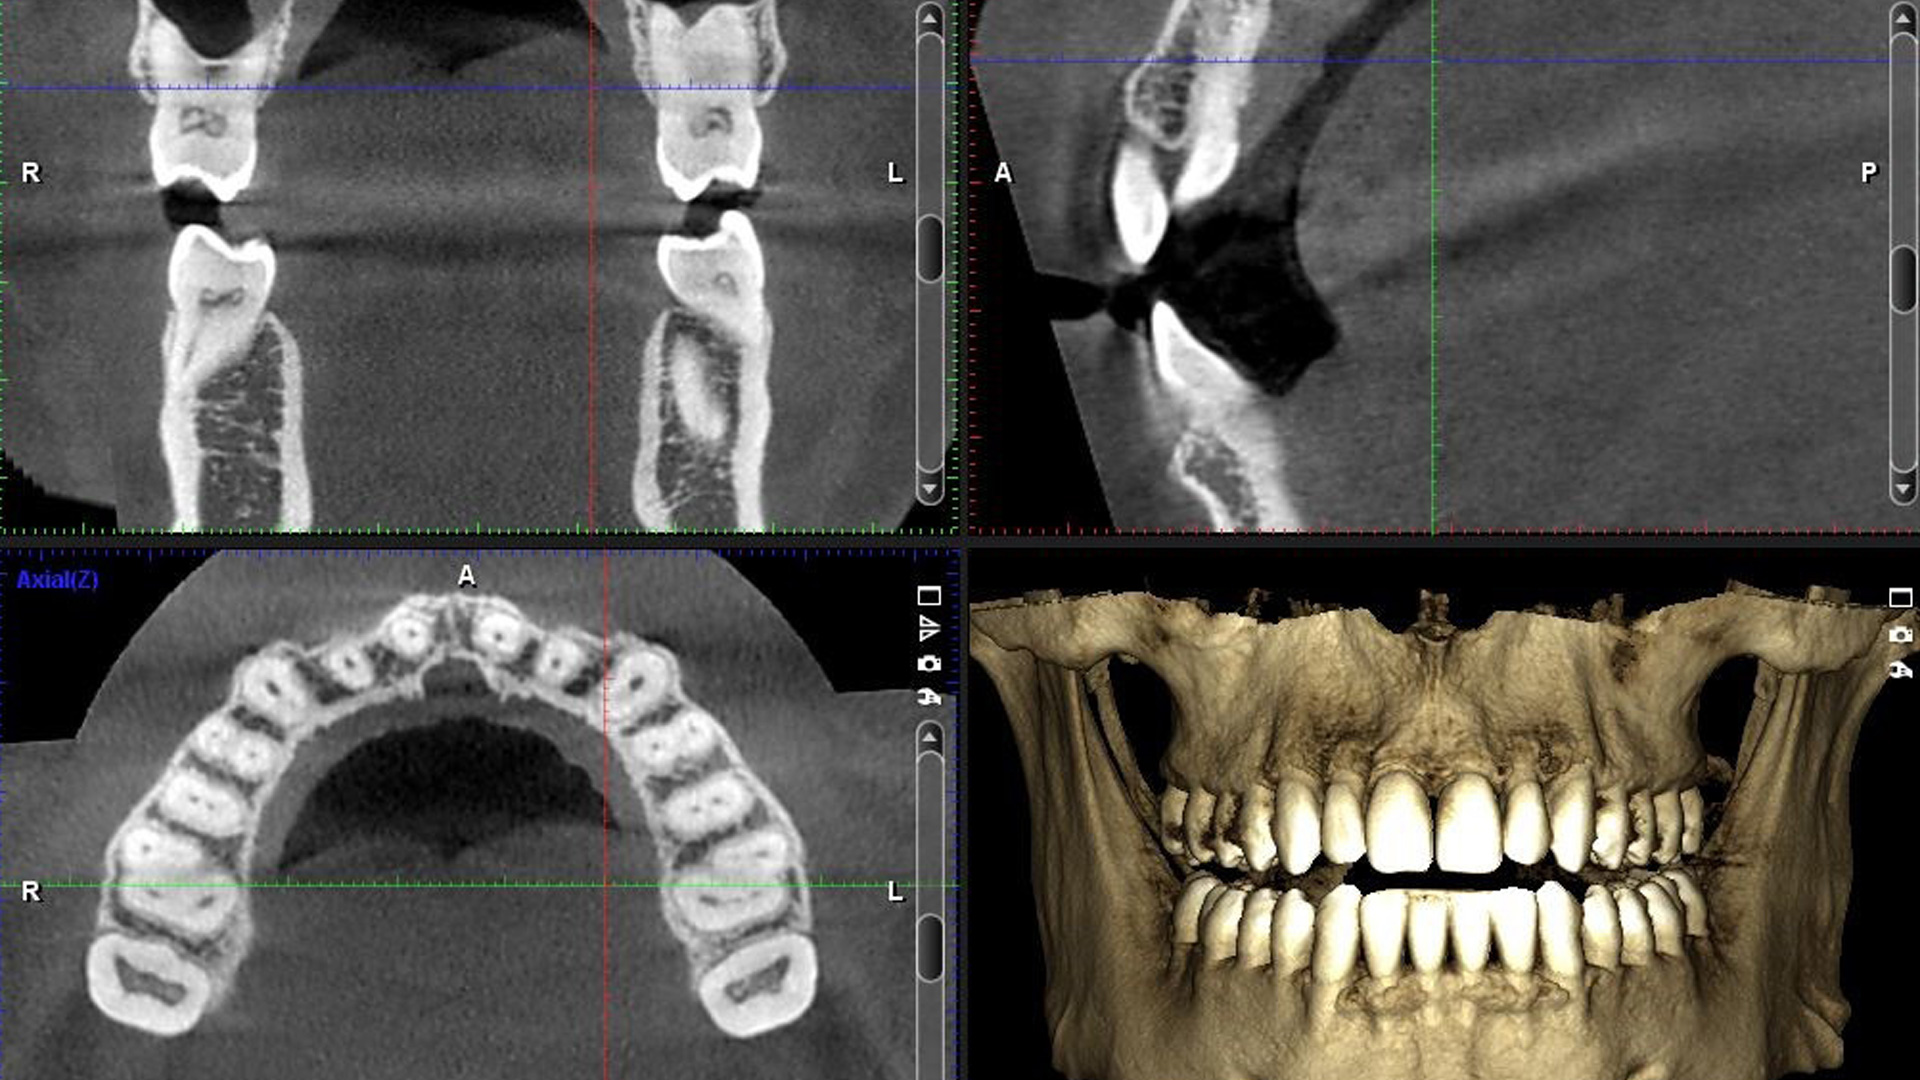

Кт зуба зачем

Кт зуба зачем 98 фото